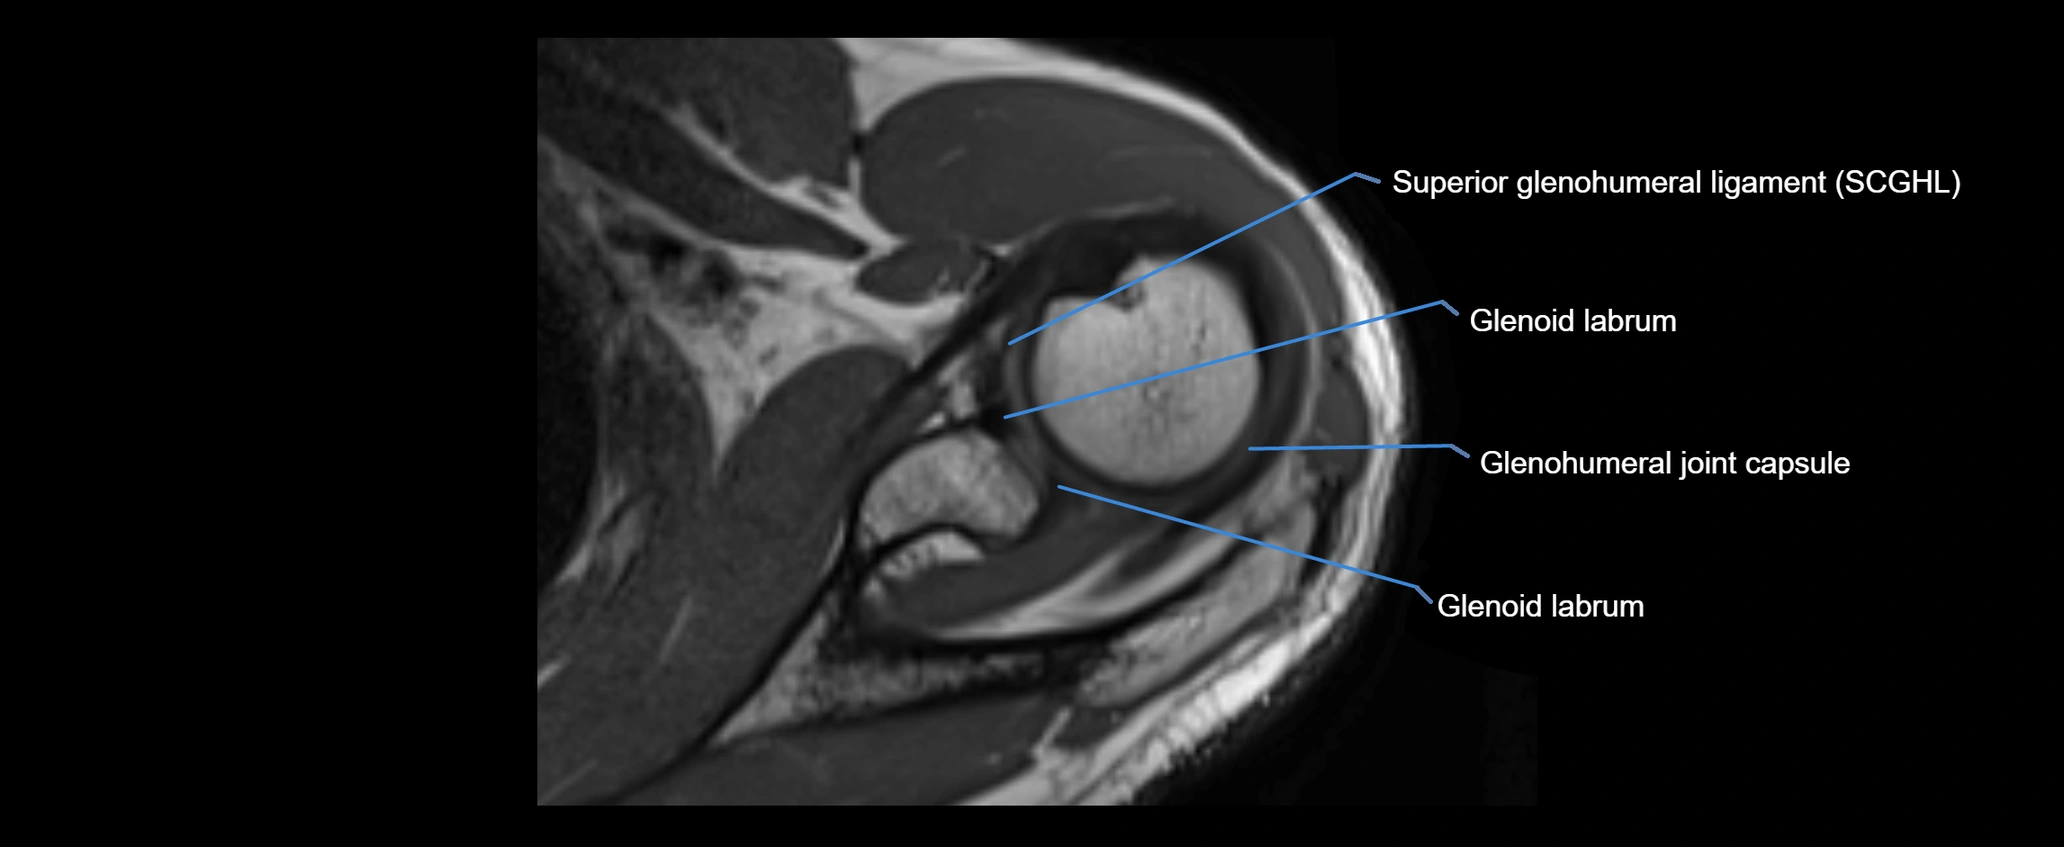

MRI images

image

MRI Appearance

• T1-weighted images:

• Normal ligament: Low signal (dark linear band) spanning acromion to clavicle.

• Surrounding fat planes: Bright, delineating the ligament clearly.

• Marrow of clavicle and acromion: Bright due to fatty content.

• Tears: Discontinuity or irregular thickening with intermediate-to-bright signal.

• Chronic injury: Thinning, fraying, or irregular low-signal fibers with adjacent scarring.

• T2-weighted images:

• Normal ligament: Low signal, homogeneous.

• Partial tear or sprain: Focal hyperintensity or thickening.

• Complete tear: Discontinuity with fluid-bright gap between clavicle and acromion.

• Associated edema: Bright signal in distal clavicle or acromion marrow.